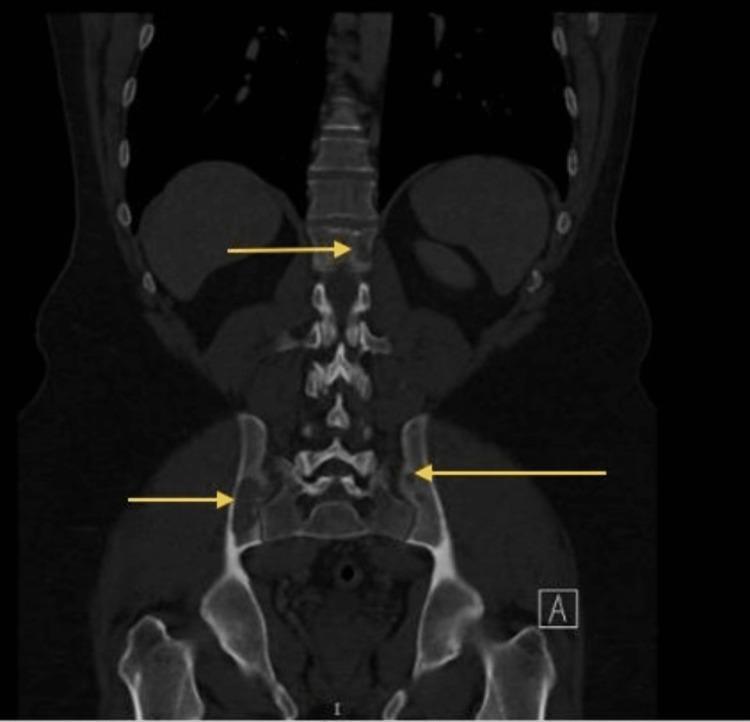

Vertebral disease is a main source of morbidity (MM) in individuals with multiple myeloma. The effects of associated osteolytic lesions and vertebral fractures on severe pain, functional limits, spinal deformity, and cord compression are well recognized. Systemic therapy, radiation, cementoplasty (vertebroplasty/kyphoplasty), and radiofrequency ablation are now available therapeutic options for severe MM spinal pain. We here reported a case of a 45-year-old male who had complained of progressive symptoms of pathological spine fractures. He had been examined and investigated for the cause of lytic lesions and found to have multiple fractures in the spine. A computed tomography (CT) revealed multiple osteolytic lesions noted in the thoracolumbar spine, ribs (bilaterally), and pelvic bones. Magnetic resonance imaging (MRI) showed a compression fracture of the T8 vertebral body with evidence of retro-bulging and a spinal canal narrowing. However, there was no evidence of spinal cord abnormal signal intensity. T2 weighted image (T2WI) keeping with edema is noted. A surgical intervention fixed the fracture and improved the quality of life. Vertebroplasty, a minimally invasive procedure, as a treatment option for vertebral lesions and pathologic fractures in the MM, showed good clinical improvement in the patient.

脊柱疾病是多发性骨髓瘤患者发病的主要原因。相关溶骨性病变和椎体骨折对剧痛、功能受限、脊柱畸形和脊髓压迫的影响已得到充分认识。全身治疗、放疗、骨水泥成形术(椎体成形术/后凸成形术)和射频消融是目前治疗严重骨髓瘤脊柱疼痛的可用治疗选择。我们在此报告一例45岁男性病例,该患者主诉病理性脊柱骨折症状进行性加重。他接受了检查并对溶骨性病变的病因进行了调查,发现脊柱有多处骨折。计算机断层扫描(CT)显示胸腰椎、肋骨(双侧)和骨盆骨有多处溶骨性病变。磁共振成像(MRI)显示T8椎体压缩性骨折,伴有后凸和椎管狭窄。然而,没有脊髓异常信号强度的证据。可见符合水肿的T2加权像(T2WI)。手术干预固定了骨折并改善了生活质量。椎体成形术作为一种微创手术,作为骨髓瘤椎体病变和病理性骨折的治疗选择,在该患者中显示出良好的临床改善效果。